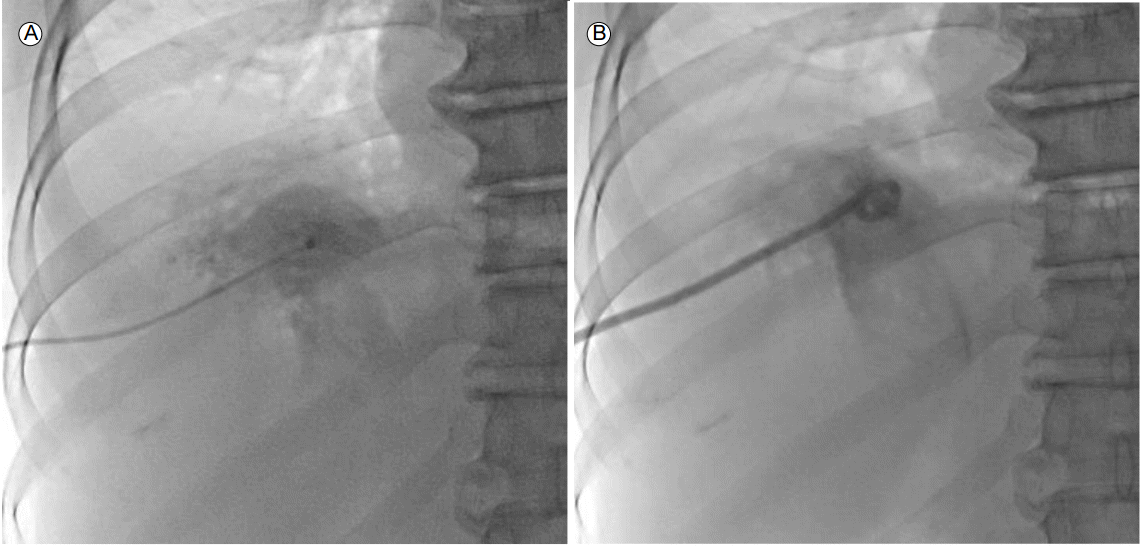

환 자: 65세 여자주 소: 2시간 전부터 시작된 허리 통증현병력: 2시간 전부터 갑자기 발생한 허리 통증으로 내원하였다. 1주 전부터 기침과 전신 근육통이 선행되었으나 특별한 치료 없이 경과 관찰하였다. 2시간 전 경부 방사통증을 동반한 급격한 허리 통증으로 이부프로펜(ibuprofen) 400 mg 복용 후에도 증상 경감이 없어 본원 응급실로 내원하였다.과거력: 고혈압, 당뇨, 결핵 및 간염 등의 병력은 모두 없었다.사회력: 음주력, 흡연력은 모두 없었다.가족력: 특이사항은 없었다.신체 문진 및 신체 검진: 경부 방사통증을 동반한 심한 허리 통증을 호소하였다. 활력 징후는 혈압 150/68 mmHg, 맥박수 102회/분, 호흡 수 30회/분, 체온 36.7℃였다. 급성 병색을 보였고 의식은 명료하였다. 복부 촉진시 우상복부의 압통이 확인되었으며 반동압통은 없었고 우측 늑골척추각 압통을 호소하였다.혈액 검사 소견: 말초 혈액 검사에서 백혈구 23,700/mm3, 혈색소 11.9 g/dL, 혈소판 249,000/mm3였다. 혈청 생화학 검사에서 혈장 포도당 120 mg/dL, 아스파트산아미노기전달효소 186 IU/L, 알라닌아미노기전달효소 106 IU/L, 알칼리성 포스파타제 68 U/L, 총 빌리루빈 2.0 mg/dL, 젖산탈수소효소 2,866 IU/L, C-반응단백질 0.89 mg/dL였다. 혈액 응고 검사에서 프로트롬빈시간 107.4%, 활성화부분트롬보플라스틴시간 20.9 second, D-dimer 10.56 μg/mL였다.방사선 소견: 단순 흉부 및 복부 방사선 사진은 정상이었다. 경부 방사통증을 동반한 심한 허리 통증을 호소하여 급성 대동맥증후군을 감별하기 위해 시행한 대동맥박리 컴퓨터단층촬영에서 간농양의 파열 및 이로 인한 거대 고름공기복증, 종격동기종 및 담도의 미만성 확장을 동반한 먼쪽총담관결석 및 담석이 관찰되었다(Fig. 1).치료 및 경과: 혈액 배양 검사 시행 후 경험적 항생제로 세포탁심(cefotaxime) 2 g 및 메트로니다졸(metronidazole) 500 mg을 8시간마다 하루 3번 정주하였고 간농양에 대하여 응급 경피배액술을 시행하였다(Fig. 2). 내원 6시간 후 호흡곤란 및 혈뇨가 관찰되면서 급격히 호흡부전 및 대사산증으로 진행하여 기관내삽관을 시행하였고 기계호흡을 위해 중환자실로 이송되었다(Fig. 3). 내원 8시간 뒤 중환자실에서 시행한 말초 혈액 검사에서 혈색소 5.0 g/dL, 혈소판 105,000/mm3 및 혈액 응고 검사에서 프로트롬빈시간 3.3%, 활성화부분트롬보플라스틴시간 180 second, D-dimer 9.35 μg/mL로 파종혈관내응고(disseminated intravascular coagulation)에 합당한 소견을 보였다. 이에 불응성 패혈쇼크에 준하여 항생제를 메로페넴(meropenem) 1 g을 하루 3번 투약하는 것으로 변경하였으며 적혈구 및 신선냉동혈장 수혈 및 최대 용량의 혈관작용약 투여와 함께 지속적 신대체요법을 진행하였으나 급격히 악화되어 내원 11시간 만에 사망하였다. 사망 후 1일 후 혈액배양 검사 3쌍 모두에서 그람양성간균이 확인되었으며 최종적으로 클로스트리듐퍼프린젠스가 동정되었다.